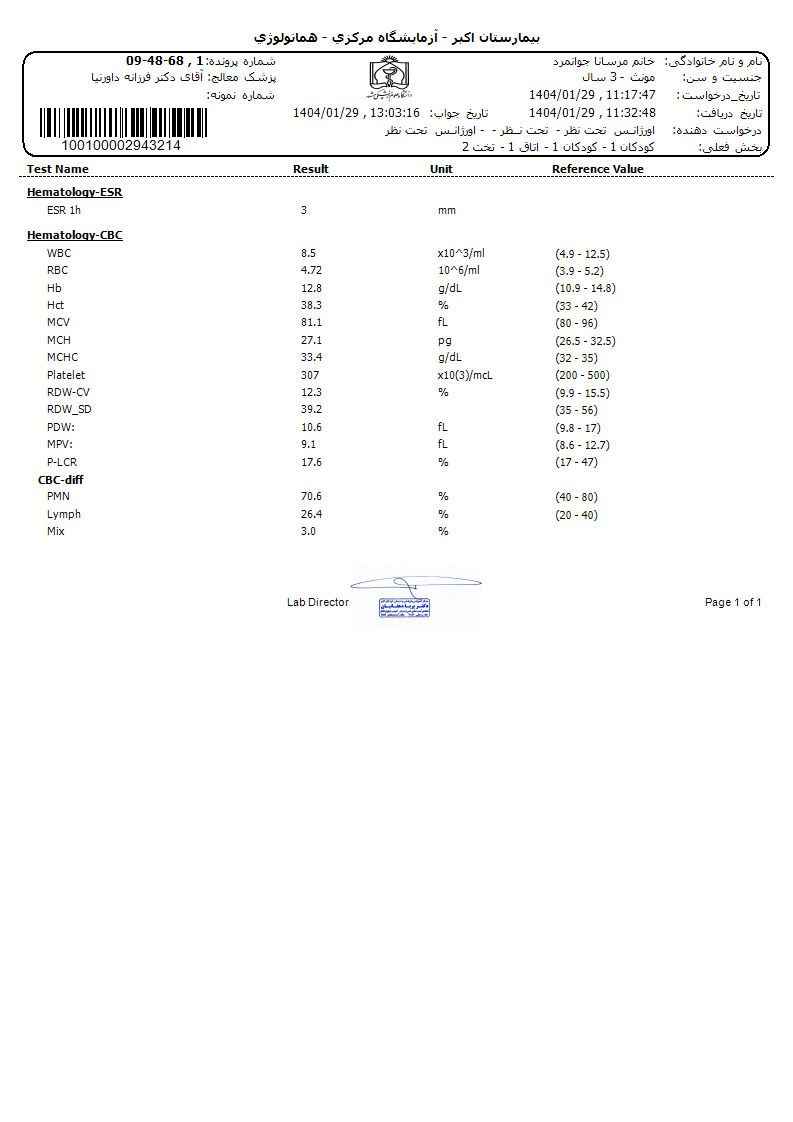

Other: